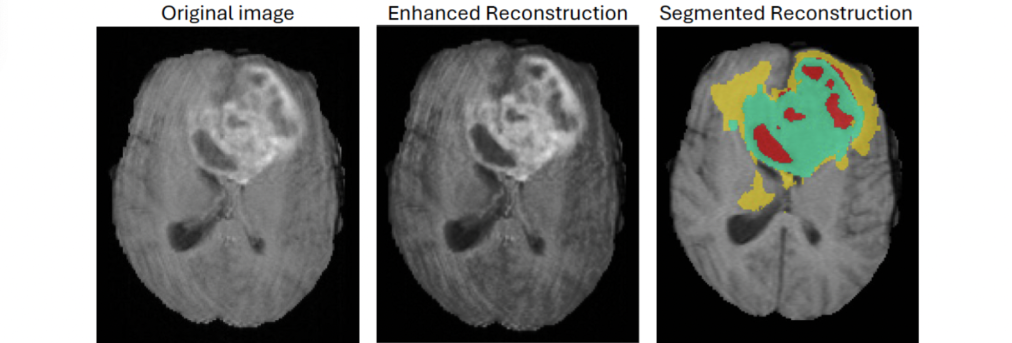

Sarah’s model improves lower-quality, pixelated scans, enhancing tissue contrast for radiologists. This allows more precise segmentation of tumors, necrotic cores, and edema, which are critical for treatment planning.

Enhanced MRI segmentation highlighting tumor regions: necrotic core (red), enhancing tumor (green), and edema (yellow), improving clarity for more precise clinical analysis and treatment planning.